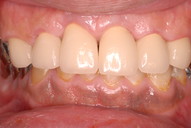

本日は前々から、歯並びと噛みあわせの悪さとそれに伴う虫歯や歯周病の予防の為に矯正を薦めていた人が、やっと決断されまして矯正をやる事になりました。

成人でもやはりあまりにも並びが悪く歯周病の進行が予想されたりしている場合は矯正をやります。それが歯の寿命を長くするからです。

ただ、一般的に子供の矯正は美容ですから注意しなくてはなりません。

ではその注意点とは。